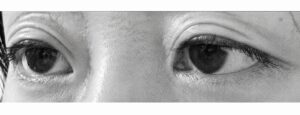

こちらは手術を受ける前の私の目(2019年)

中程度の眼瞼下垂症と診断されました。

そして一応二重なんですが、上に瞼が皺のようになっていますね^^;

さぁ、ご覧ください。

これが完成した私の目

向かって左は二重の幅がぶっとく、右は二重の始まりの位置が変で上に皺もあります。